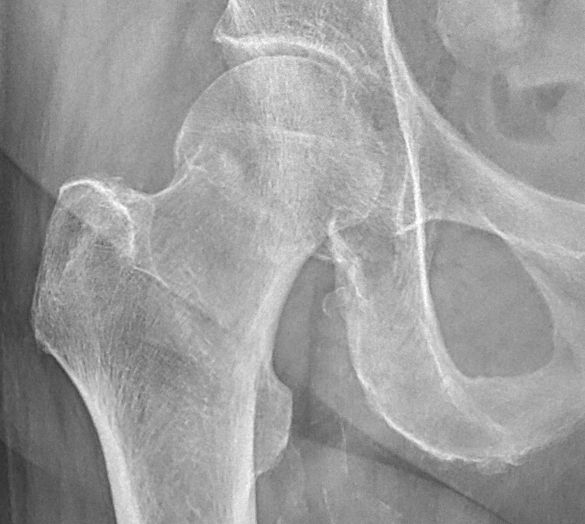

- Cervikal, fraktur av kollum femoris. Klassificeras enligt Garden som bedöms på frontalbild. Det finns något olika tolkningar av denna klassifikation. Ofta används istället "Garden 1-2" för odislocerad eller måttligt dislocerad fraktur och "Garden 3-4" för mer dislocerad.

- Garden 1: inkomplett fraktur med intakt inferior kant, kan vara valgusställd [1]